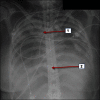

Methods: An ECMO transport team implanted an ECMO at the site of the primary care center with subsequent transport of the patient to the tertiary care center. Between September 2009 and March 2011, six patients with ARDS were treated by our ECMO transport team. Mean age was 39.5±12.0 years. All implantations were done percutaneously in a veno-venous configuration.